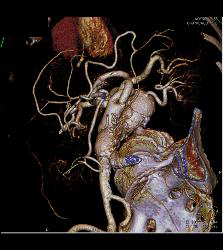

3D of Iliac Arteries